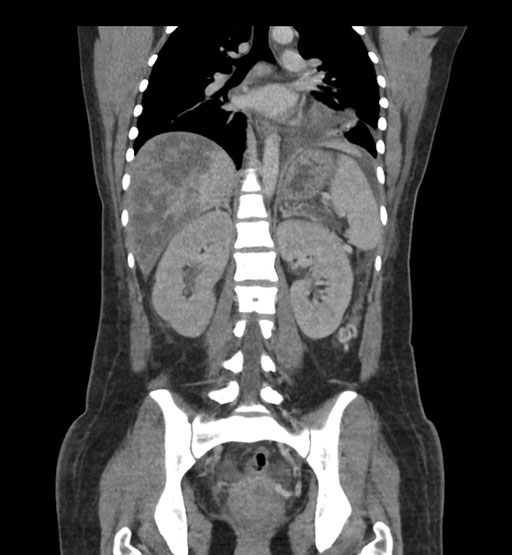

Coronal Arterial

Imaging analysis

Based on initial findings, which issue(s) would you be most concerned about?